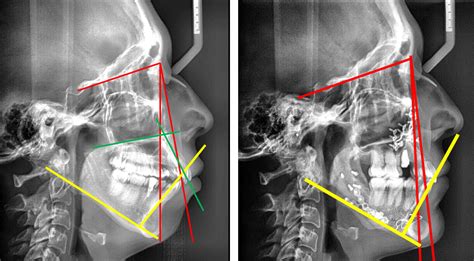

En la siguiente radiografía lateral inicial se puede observar la mordida abierta de unos 3mm (izquierda), en la radiografía lateral final (derecha) se puede observar una sobremordida de 3mm, es decir, hemos conseguido unos 6mm de movimiento vertical a nivel de los incisivos.

Radiografías laterales de antes durante y después del tratamiento.